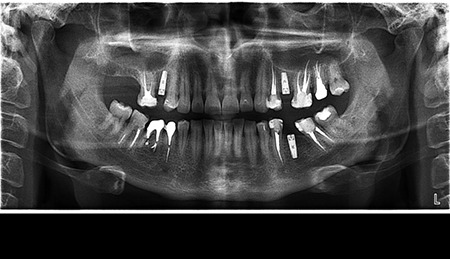

- Цифрова панорамна рентгенографія (ортопантомограма) – дає цілісне зображення всієї щелепно-лицевої системи.

Що ви уявляєте, коли лікар говорить про ортопантомограму? Насправді, це знімок усієї зубощелепної системи, який охоплює обидві щелепи, гайморові пазухи та скронево-нижньощелепні суглоби. Таке оглядове фото дозволяє стоматологу отримати загальне уявлення про стан зубів, кісткових структур та навколишніх тканин.

Ортопантомограма Полтава є незамінною при первинній діагностиці, коли потрібно оцінити загальний стан ротової порожнини. Її призначають у наступних випадках:

Цифрова панорама Полтава успішно використовується для первинної діагностики в момент першого звернення до лікаря, бо дозволяє виявити всі патологічні процеси в зубах, кістці, навколощелепних тканинах. Завдяки їй лікар не припуститься помилок під час планування й виконання складних ортопедичних робіт.

Діагностика зубів Полтава із застосуванням ортопантомограми має ряд переваг: